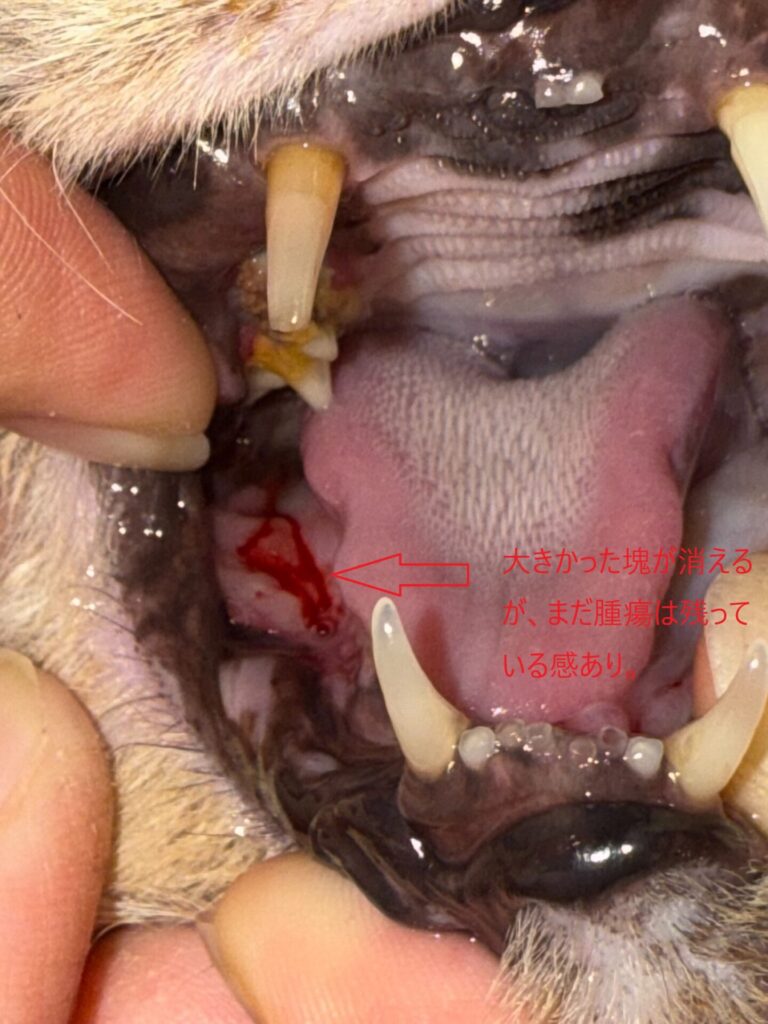

左下顎部 ⇩

下顎部も順調に縮小傾向です。

も少し腫瘍の硬結がある感じです。